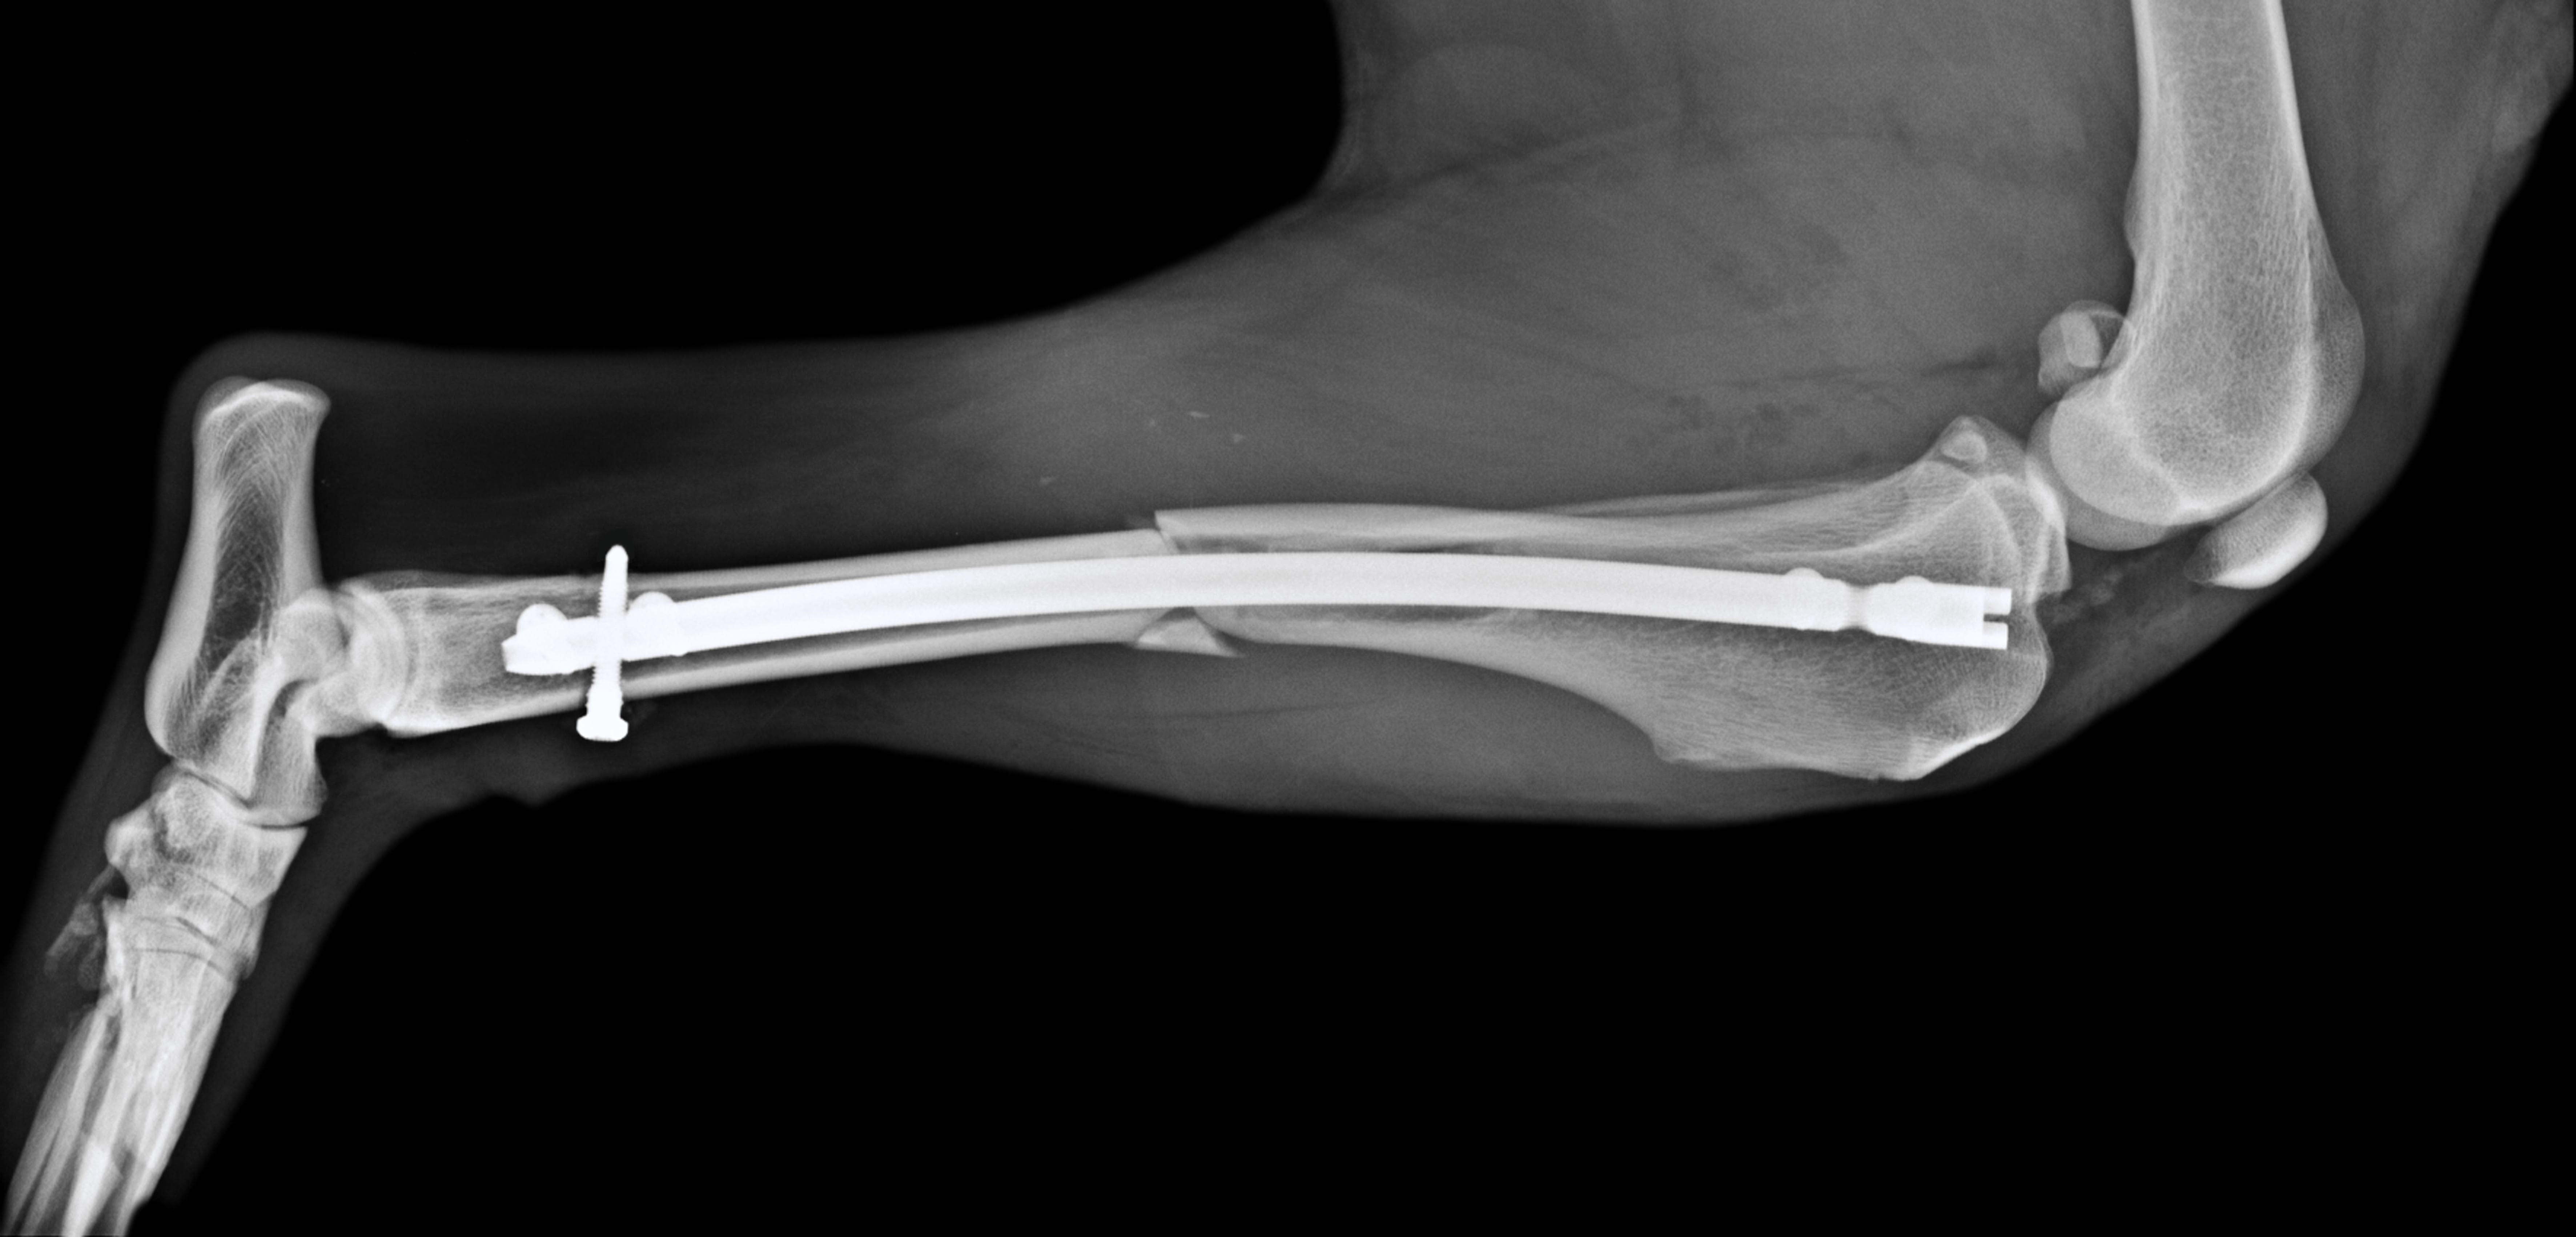

Surg’X offers the first angle-stable, anatomical, titanium interlocking nail for the treatment of long bone fractures in small animals.

- Anatomical curved nail

- Advanced multi-planar locking system